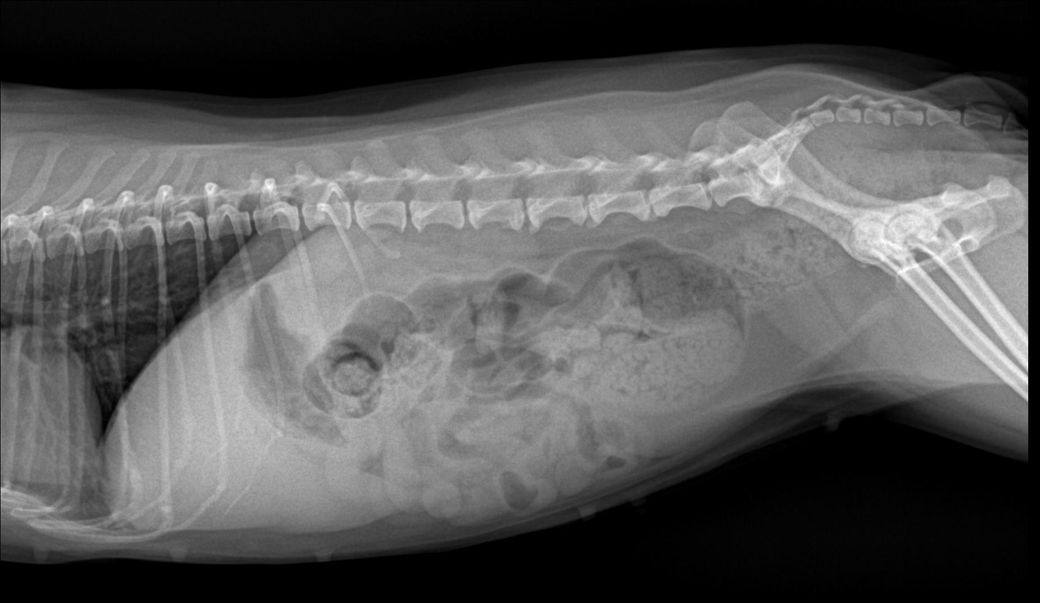

X-ray판독부탁드려도될까요?

경추 4-5-6번의 추간판 사이가 좁아보이며 동시에 복부 방사선 촬영 시 결장에 가스가 많이 차 있는 것을 볼 수 있습니다.

복통이나 설사가 있을 수도 있겠네요

엑스레이 판독은 병력과, 신체검사 및 다른 검사 지표들을 종합적으로 보고 판단하는것이지 사진만 가지고 평가하는게 아닙니다. 사진만 보고 판단하니 수의사들마다 차이가 클 수밖에 없는것이고, 신체검사를 직접 한 주치의의 판단이 가장 정확한것이니 주치의의 의견을 따르시기 바랍니다.